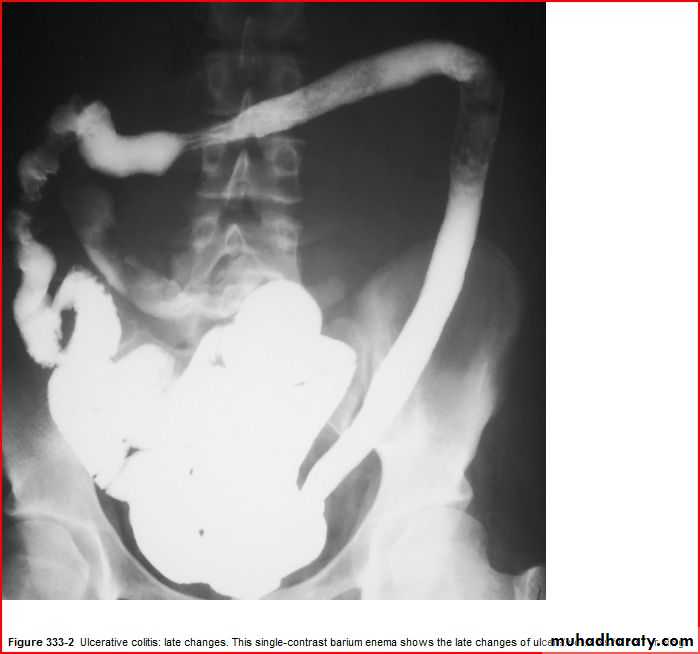

Leadpipe apperance

Barium enema